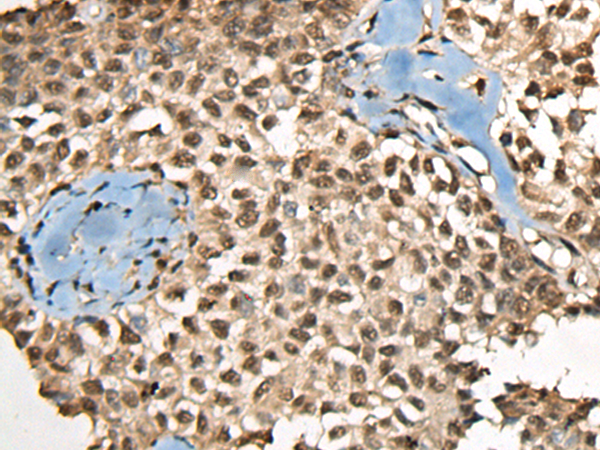

分类: 科研抗体货号: P09455别名: ST6N; SIAT1; ST6GalI应用: IHC反应种属: Human, Mouse, Rat